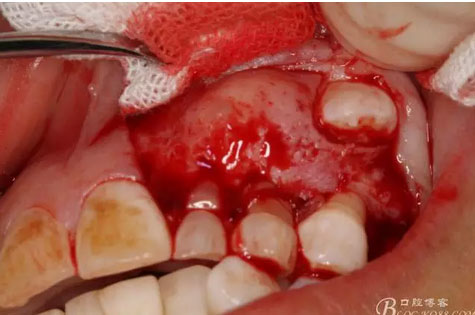

圖13.暴露出部分牙瘤

圖14.沿一側骨壁逐步剝離牙瘤組織。

圖15.剝離出來的多個成型小牙齒及致密鈣化物。

圖16.形態(tài)各異的小牙齒。

圖17.呼之欲出的巨大牙瘤組織。